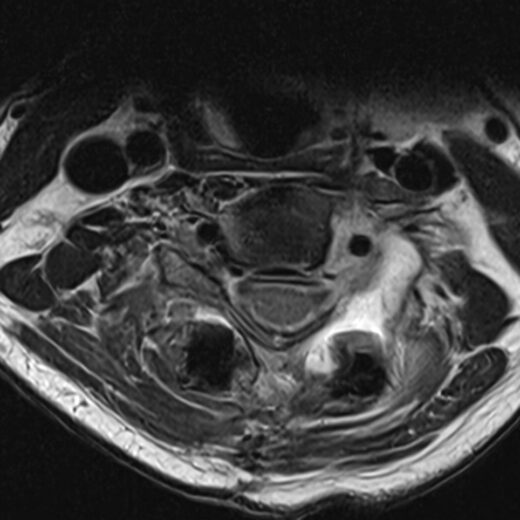

The CMORE® Cervicothoracic (CT) System is an enhanced set of instruments and implants for posterior stabilization of the cervicothoracic spine. The world’s first spinal implants made of nonmetallic and radiolucent BlackArmor® technology now enable a full spectrum of treatment modalities in adjuvant tumor therapy and enhance postoperative imaging diagnostics in the cervicothoracic spine.

- BlackArmor® material is radiolucent in all diagnostic imaging modes and facilitates adjuvant radiation treatment

- The first tulip made of BlackArmor® material for artifact-free CT and MRI imaging